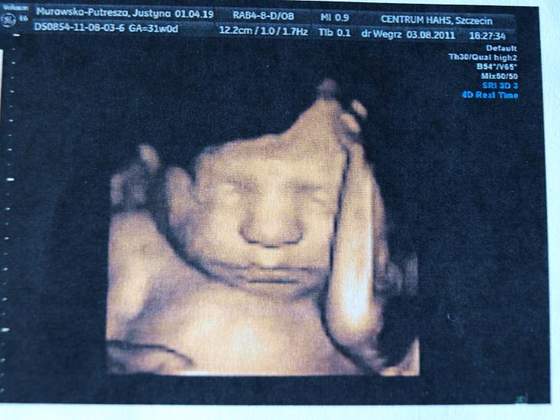

Ja po usg 30tyg na którym byłam równo w 31 tyg :)

A więc synuś pozostał synusiem, pięknie jajeczka mamusi pokazał :)

Waga 1678g wszystko jest w porządku, zdrowiutki to najważniejsze :)))

Zobacz załącznik 378181Zobacz załącznik 378182

jaki slodziak :) super , ze wszystko dobrze wyszlo !!!